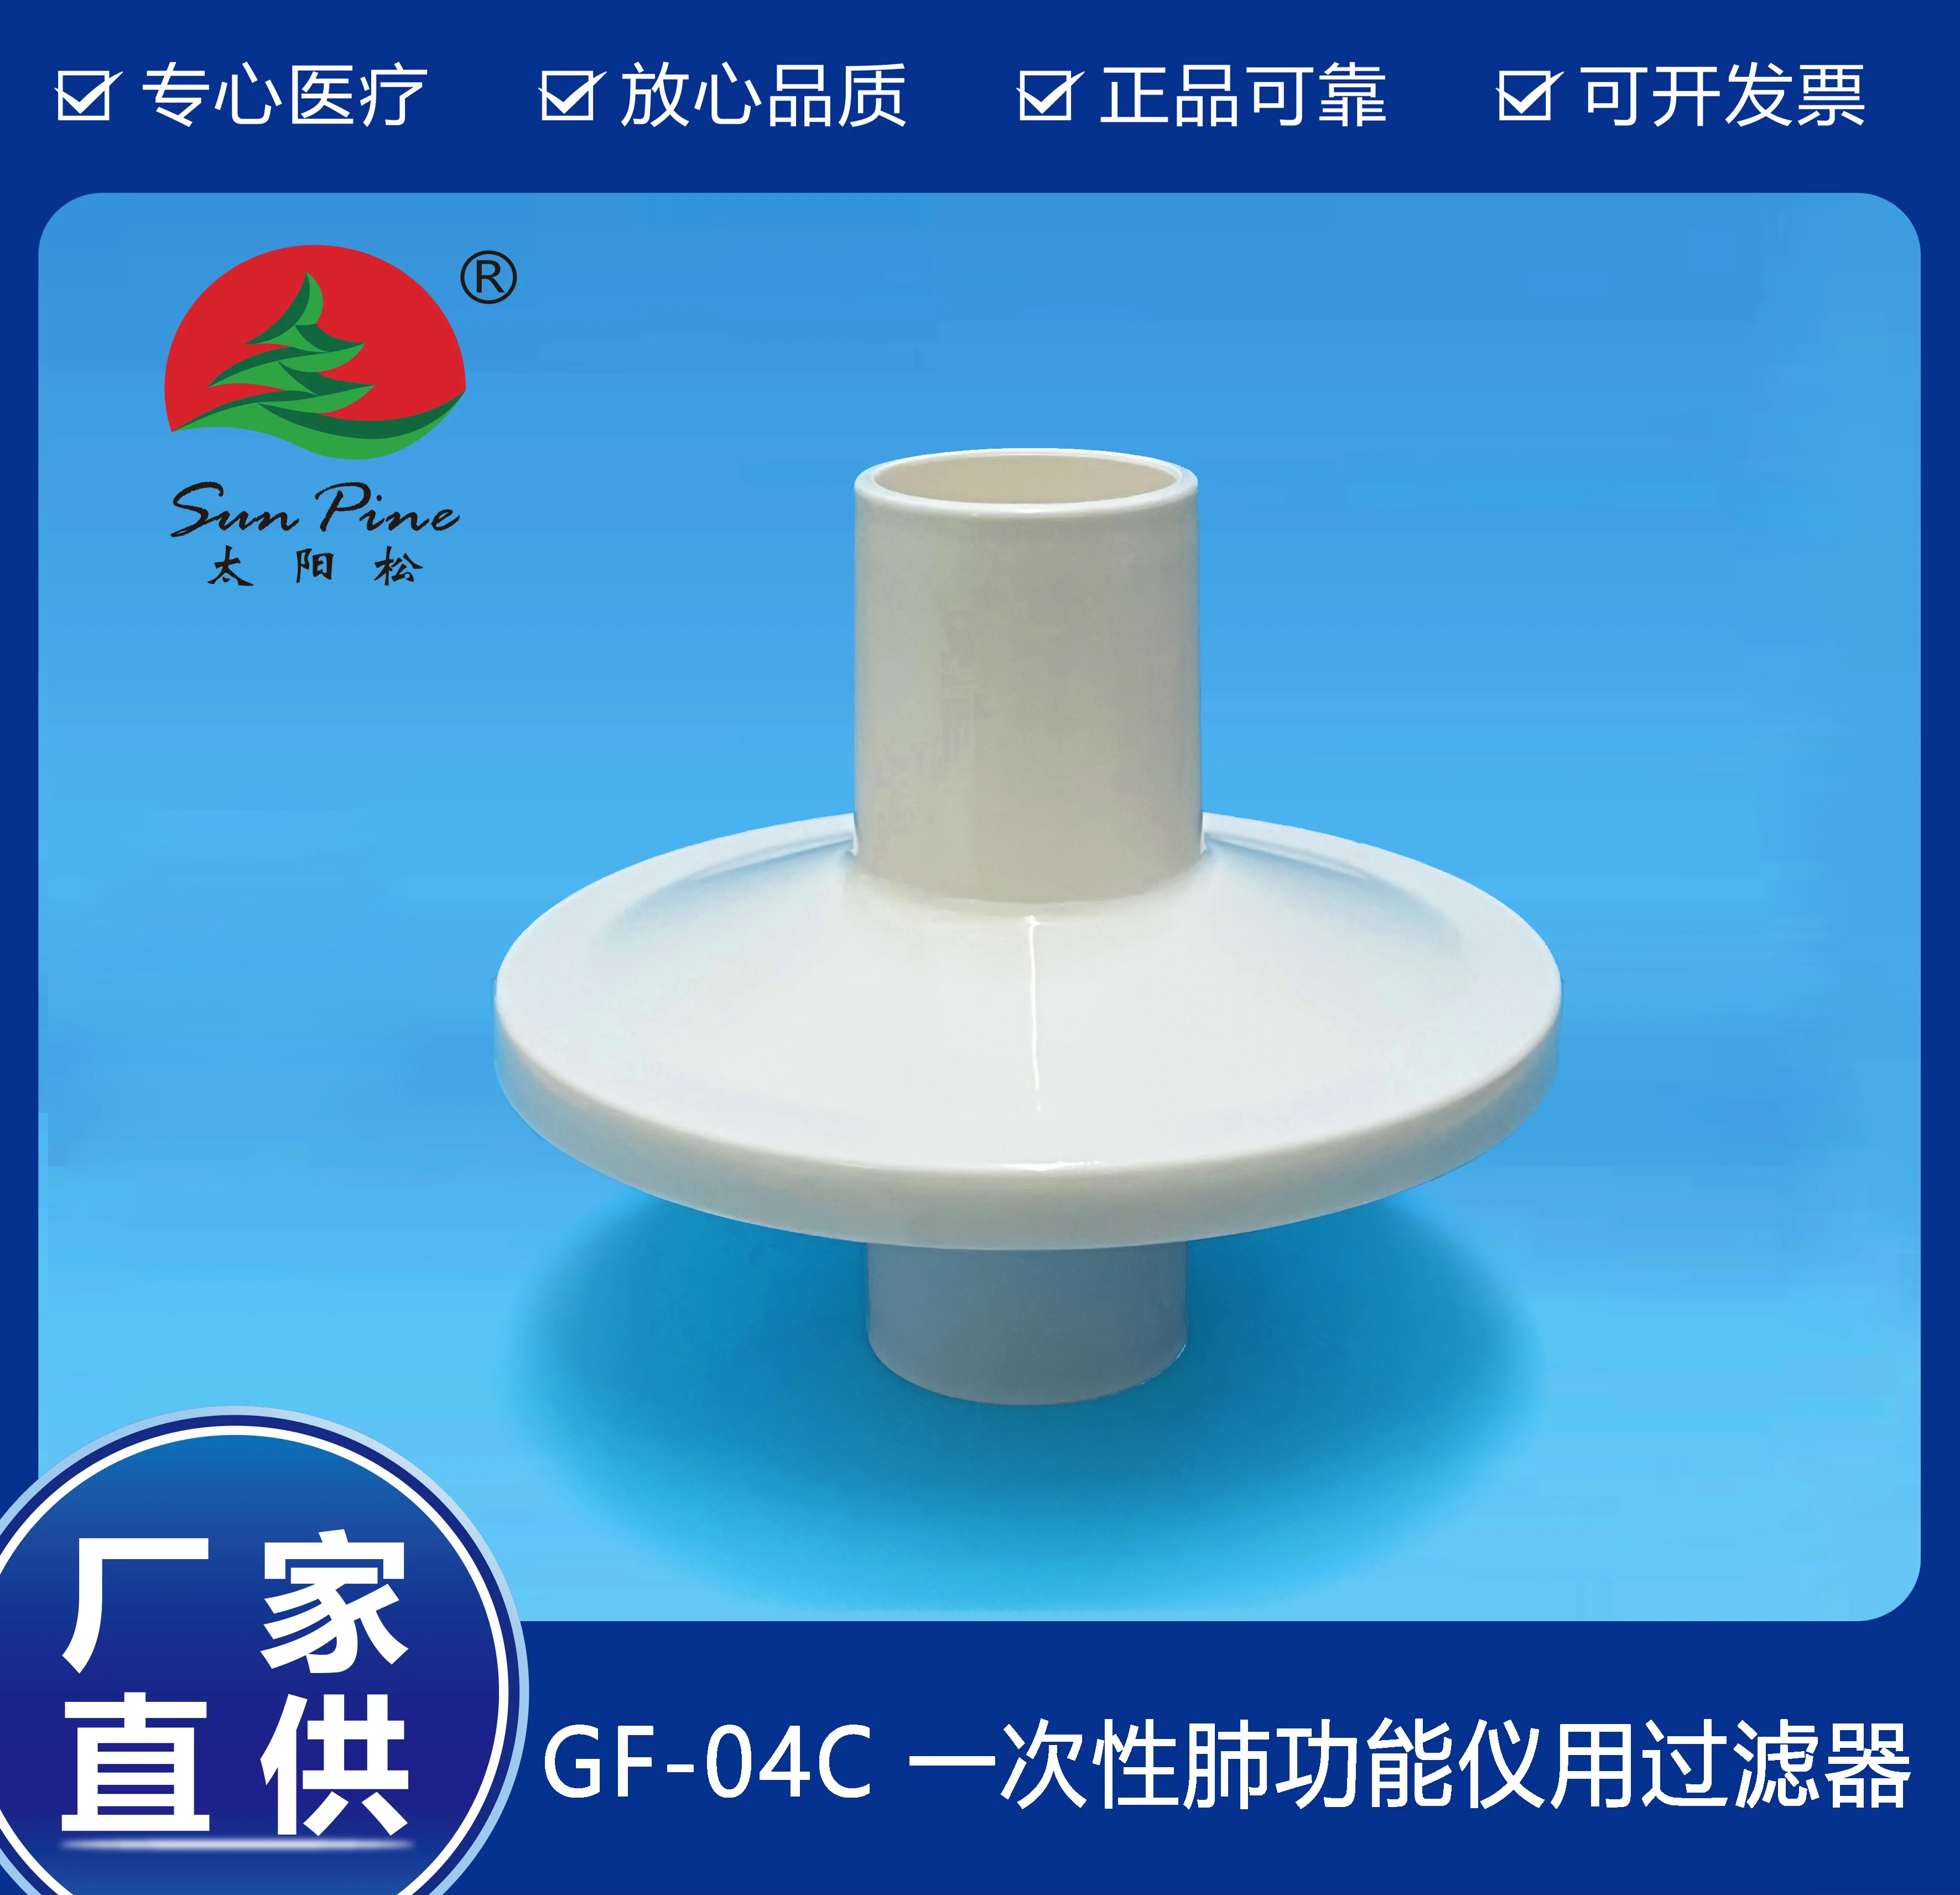

中山高榮電子科技有限公司是一家集自主研制,生產(chǎn)和銷(xiāo)售一體的高新技術(shù)醫(yī)療器械生產(chǎn)企業(yè),嚴(yán)格按照CFDA認(rèn)證,遵守國(guó)家醫(yī)療器械法規(guī)建立了完善的質(zhì)量管理體系,確保提供給客戶(hù)的醫(yī)療器械產(chǎn)品安全健康。公司擁有十萬(wàn)級(jí)、萬(wàn)級(jí)潔凈生產(chǎn)車(chē)間,環(huán)氧乙烷滅菌車(chē)間,有專(zhuān)門(mén)的物理實(shí)驗(yàn)室、理化實(shí)驗(yàn)室和微生物實(shí)驗(yàn)室以及醫(yī)電研發(fā)室、醫(yī)電生產(chǎn)車(chē)間。主要產(chǎn)品有:“太陽(yáng)松”品牌:一次性使用呼吸過(guò)濾器,一次性肺功能儀用過(guò)濾器,咬嘴;“凱華”品牌:醫(yī)用電子產(chǎn)品,肺功能檢查儀等,其中過(guò)濾器,咬嘴可匹配市場(chǎng)上各種不同品牌型號(hào)的肺功能儀使用,可以降低患者吸入或呼出顆粒性物質(zhì)的數(shù)量,防止污染儀器,大限度保障每位受測(cè)者健康安全.